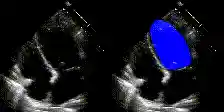

Examples

We show examples of our semantic segmentation for nine distinct patients below. Three patients have normal cardiac function, three have low ejection fractions, and three have arrhythmia. No human tracings for these patients were used by EchoNet-Dynamic.

| Normal | Low Ejection Fraction | Arrhythmia |